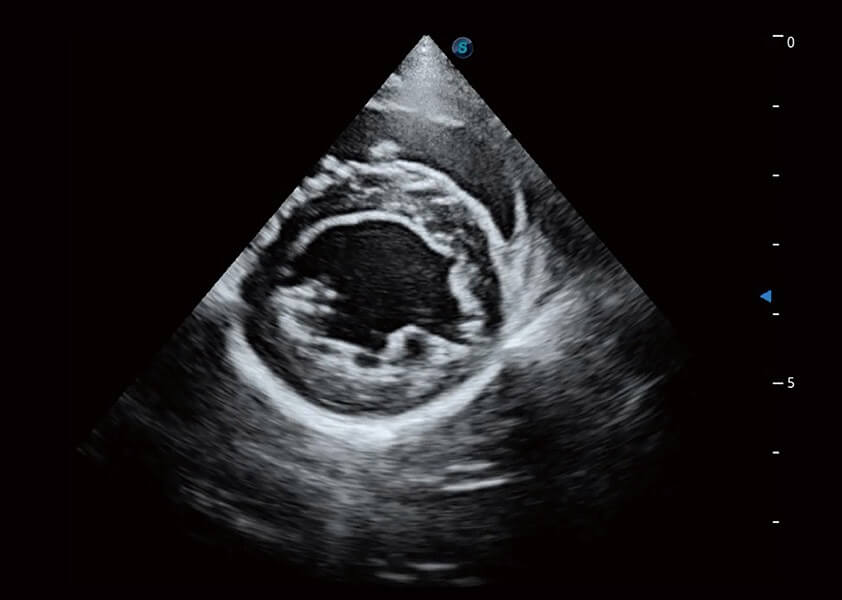

ProPet 60 作為一款高端臺式動物超聲設(shè)備,為動物醫(yī)生的日常診斷提供了一系列貼合動物臨床需求、解決臨床實際問題的高級成像功能。憑借全系列高清探頭,滿足醫(yī)生對腹部、心臟、生殖、淺表、肌骨等成像的所有需求,切實幫助您提升檢查效率,提高診斷信心。